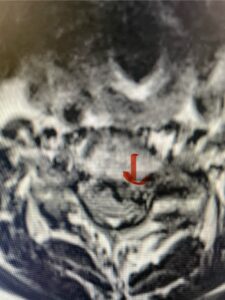

The next patient is a 54 year-old male who presents with 3 years of neck pain with associated numbness and tingling of his extremities. Patient had had physical therapy, chiropractic care, and epidural steroid injections with no significant relief. The patient on exam had weakness in a long tract distribution on the left. MRI revealed four level disc disease from C3-4 to C6-7 with a moderate kyphosis and cord compression and signal change at C3-4 (Fig. 9). Because of the kyphotic deformity it was decided to perform a four-level anterior cervical discectomy and interbody cage at each segment as well as plate. The patient had significant osteophyte disease at each level which required a high-speed drill to shave down the osteophytic disease and remove and decompress the foramina with fine Kerrison. Intraoperative imaging revealed good placement of the cages and plate at each level (Fig. 10). The patient had good relief of his preoperative symptoms.

Fig. 9a Sagittal T2-weighted cervical MRI demonstrating severe upper cervical spinal cord compression secondary to C2 anterior subluxation on C3 with development of thickened posterior degenerative material (red arrow)